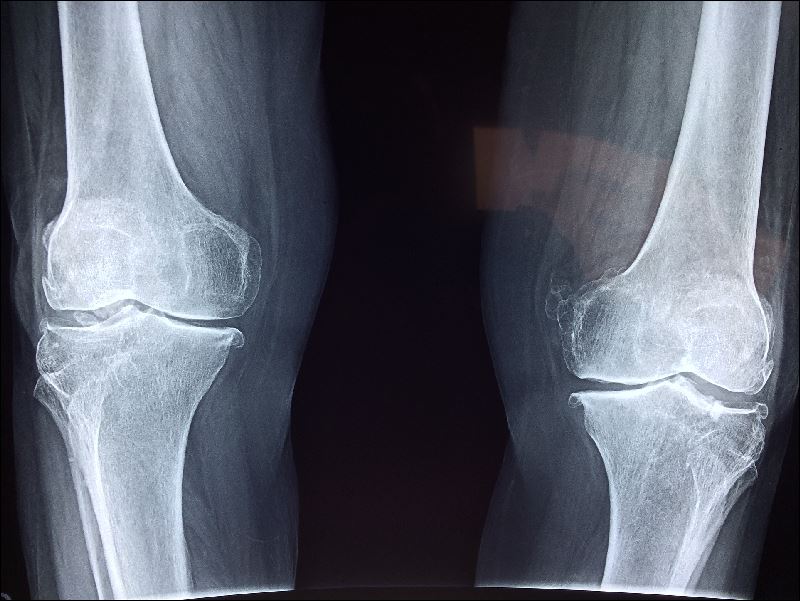

4cm 이상 신장이 줄어든 사람은 적극적으로 골밀도 검사나 엑스레이 검사를 받도록 권장하고 있습니다.

검사 방법 문진 의사로부터 골다공증에 관한 질문이 있어요. 현

재 신경이 쓰이는 증상에 관한 것 이외에도 폐경 시기나 병력, 식사와 운동, 생활 습관에 관한 것 등 다양하지만 이들은 진단하는 데 중요한 단서가 됩니다.